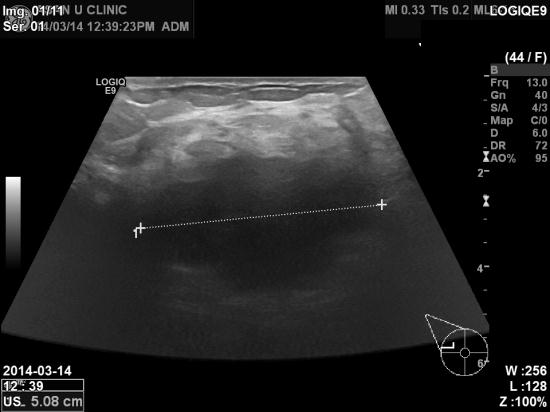

우측유방에 멍우리가 만져져 내원하신 44세여자분이십니다.

본원 초음파 검사상 우측유방에 5cm 가 넘는 혹이 발견되었고,